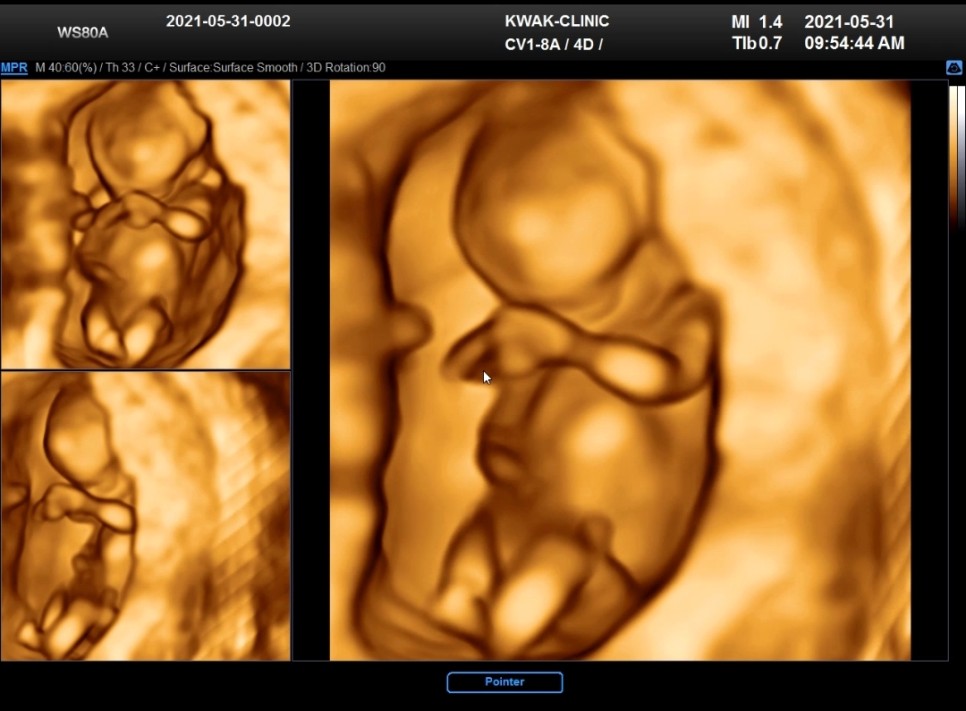

12주차가 되면 1차 정밀 초음파를 받습니다

평소 아기가 건강한지, 양수의 양과 경부의 길이가 괜찮은지를 5분 전후로 확인한 경우 정밀 초음파는 약 10분 전후로 자세히 보고 진행합니다.

이 때 태아의 목 투명띠 두께를 측정하여 인터그레이티드 통합검사를 동시에 실시합니다.다운증후군, 에드워드 증후군, 신경관 결손 등의 검사로 태아의 건강한지 여부를 확인합니다.(일명 기형아 검사)

곽여성병원의 정밀초음파는 담당의사가 아니라 초음파실에서 다른분이 봐줬거든요

초음파 당일 두께를 알려주고 정상범위라고 해서 일단 안심했습니다 (3mm 이상이면 위험도가 높습니다)

그리고 마지막에 입체 초음파까지 볼 수 있어서 좋았어요 ㅎ_ㅎ(정밀초음파후 담당의사와 짧은 상담진료는 진행합니다)

12주차인데 벌써 아기 모습이 많이 만들어져서 신기해요.양손을 모은 통통이가…♡귀엽구나 너